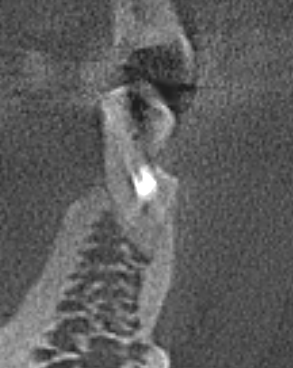

nau_63 Опубликовано 27 октября, 2025 Поделиться Опубликовано 27 октября, 2025 Добрый день. Нижняя 5-ка слева. Сильный клиновидный дефект. Зуб депульпирован и для прочности установлен штифт. Сбоку была пломба, но быстро отвалилась. При надавливании на зуб в сторону языка есть не сильная боль. Предполагаю, что при надавливании происходит изгиб в тонком месте и штифт смещается, вызывая боль. При жевании, вертикальном надавливании и надавливании наружу боль отсутствует. В кабинете протезирования предложили клиновидный дефект запломбировать, сразу зуб обточить (пока пломба не отвалилась) и поставить коронку. Прошу совета - будет ли в этом случае коронка прочно держаться и будет ли вся конструкция прочной при боковой нагрузке? Может быть есть другие варианты протезирования? Какой вариант (на Ваш взгляд) предпочтительней? Соседняя 6-ка отсутствует, планирую имплант. Ссылка на комментарий

Doc Опубликовано 1 ноября, 2025 Поделиться Опубликовано 1 ноября, 2025 Эти срезы неинформативны. В целом вкладку можно установить на любой зуб, однокорневой, многокорневой — неважно, но информации маловато для того, чтобы что-то советовать конкретное. 1 Ссылка на комментарий

nau_63 Опубликовано 11 ноября, 2025 Автор Поделиться Опубликовано 11 ноября, 2025 В 01.11.2025 в 22:14, Doc сказал: Эти срезы неинформативны. В целом вкладку можно установить на любой зуб, однокорневой, многокорневой — неважно, но информации маловато для того, чтобы что-то советовать конкретное. У меня есть КТ. По нему можно сделать выводы? Ссылка на комментарий

red_butler Опубликовано 11 ноября, 2025 Поделиться Опубликовано 11 ноября, 2025 2 часа назад, nau_63 сказал: У меня есть КТ. По нему можно сделать выводы? Здравствуйте, покажите фото во рту. И залейте кт в облако, например яндекс, и вставьте в сообщение ссылку. Но учтите, что скачать кт смогут или захотят не все доктора. Ссылка на комментарий